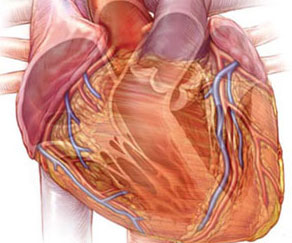

Eric T. Olson Illustration & Design

Eric T. Olson is an accomplished medical illustrator with over a decade of experience creating professional medical illustrations, graphics, and animations for major companies with expertise ranging from patient education to pharmaceutical training. His client list includes such names as Medtronic, Krames Patient Education, Boston Scientific, Novartis, and WebMD.

Eric is well-versed in the use of technology to ensure that the medical imagery he creates is appropriate to fit the needs of the viewer. By combining this technology with fundamental illustration skills, he delivers effective imagery that is equally informative, accurate, and visually appealing.